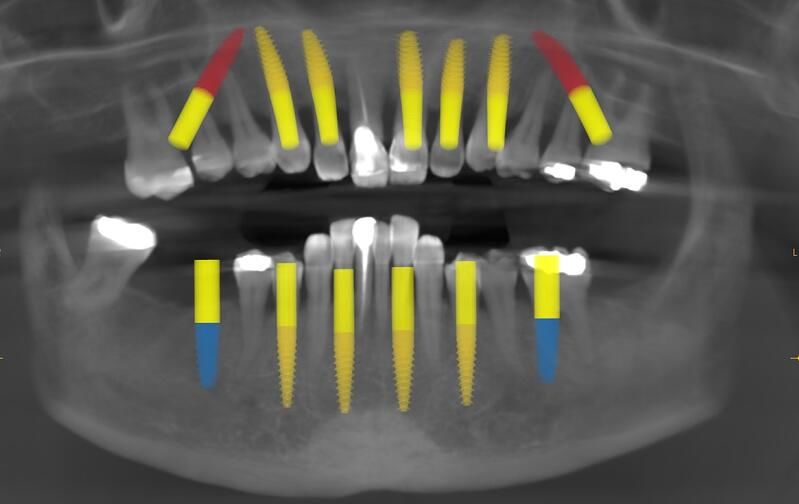

完成植入后全景照片